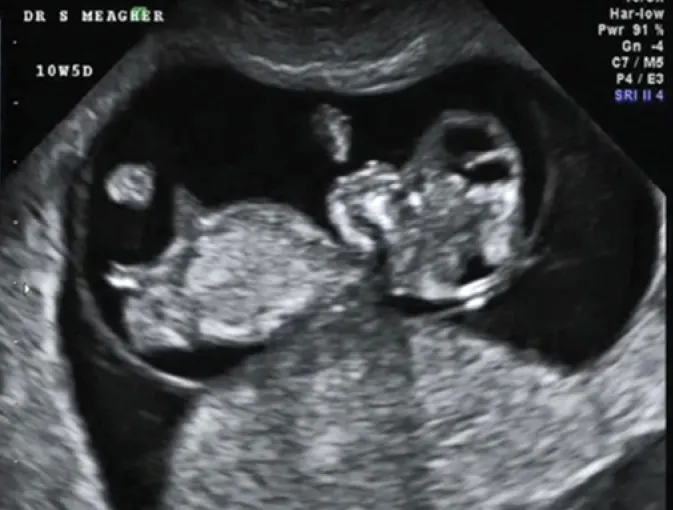

分享一個33歲女性懷孕13週又6天診斷無顱畸形(acrania)。通稱Acrania–exencephaly–anencephaly sequence(AEAS),從無顱骨到無腦症是一個持續進展的過程。

- 超音波finding(第一孕期)

羊水混濁(increased echogenecity of amniotic fluid):在羊水裡消失的腦組織造成的,也會有羊水過多的現象

Mickey mouse sign:雙葉型的腦組織

Beret sign:裸露的腦組織因為無顱骨的包覆,往前突出,可區分exencephaly與anencephaly

頭臀徑會比預期的週數還要小

可使用陰道超音波確認顱骨及腦部的異常